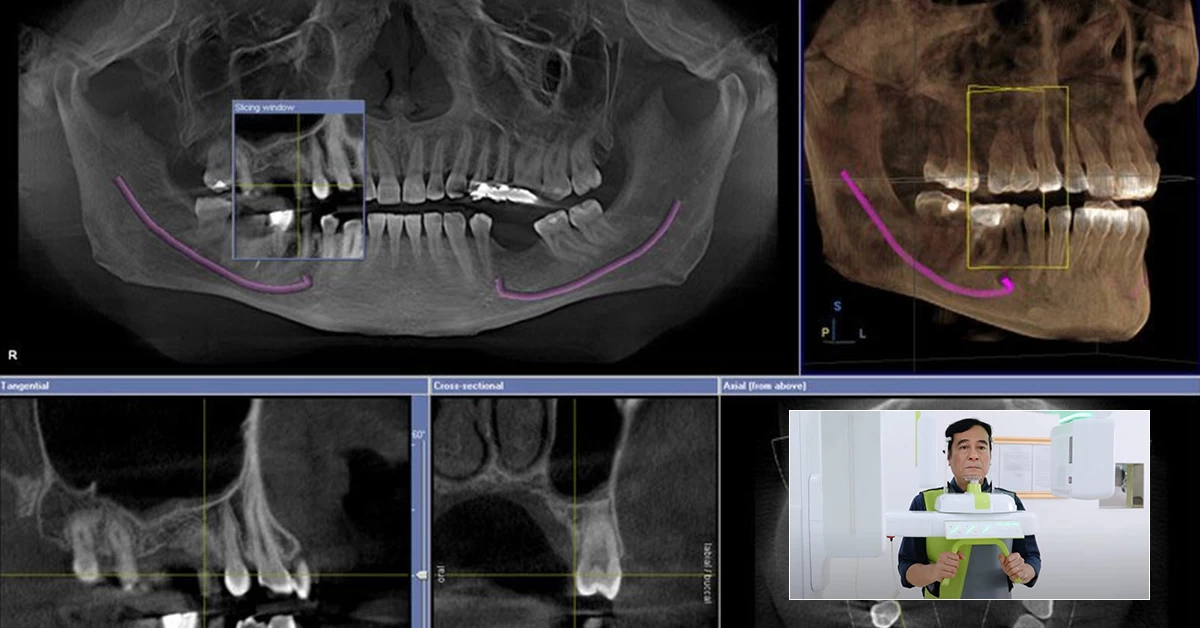

Nha khoa Lạc Việt Intech là đơn vị độc quyền áp dụng công nghệ trồng răng implant Safe Tech – công nghệ trồng răng implant tiên tiến nhất hiện nay. Công nghệ Safe Tech là sự kết hợp của bộ đôi công nghệ Smart Tech và Stop Hurt giúp các bác sĩ lên kế hoạch điều trị chính xác, trực quan trong không gian 3 chiều, lựa chọn vị trí cấy ghép implant tốt nhất, cấy ghép implant nhanh chóng, không sưng, không đau, không chảy máu…

Với công nghệ trồng răng implant Safe Tech, khách hàng sẽ được lên kế hoạch điều trị bằng công nghệ AI giúp lựa chọn vị trí cắm trụ implant tốt hơn, thực hiện cấy ghép implant nhanh chóng và chính xác hơn. Từ đó mang lại kết quả như mong đợi, vừa phục hình răng mất khôi phục khả năng ăn nhai vừa cải thiện thẩm mỹ đáng kể.

Luôn đặt chất lượng điều trị lên hàng đầu, nha khoa Lạc Việt Intech trang bị đầy đủ hệ thống trang thiết bị hiện đại như: máy chụp phim CT Cone Beam cho hình ảnh cấu trúc xương rõ nét trong 3 chiều không gian; máy Scan toàn hàm iTero Element 5D scan toàn hàm chỉ với 60s; hệ thống ghế nha hiện đại, thoải mái… Quá trình chụp phim, thăm khám và điều trị đều được diễn ra tại nha khoa mà khách hàng không cần chụp phim X-Quang ở nơi khác.

- Máy chụp Phim X-quang CT Conebeam